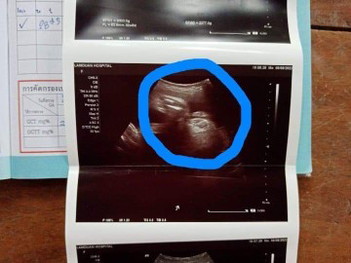

ซาวมาล่าสุดวันนี้ผู้หญิงซาวกี่รอบหมอก็บอกว่าผ.ญแต่ทำไมจิมิน้องดูใหญ่จังค่ะคุณแม่สงสัยมาก34+3วิค

อาจจะเป็นมุมที่หมอกดถ่ายภาพมาเฉยๆค่ะ ถ้าหมอไม่ได้แจ้งว่ามีความผิดปกติก็ไม่ต้องกังวลนะคะ